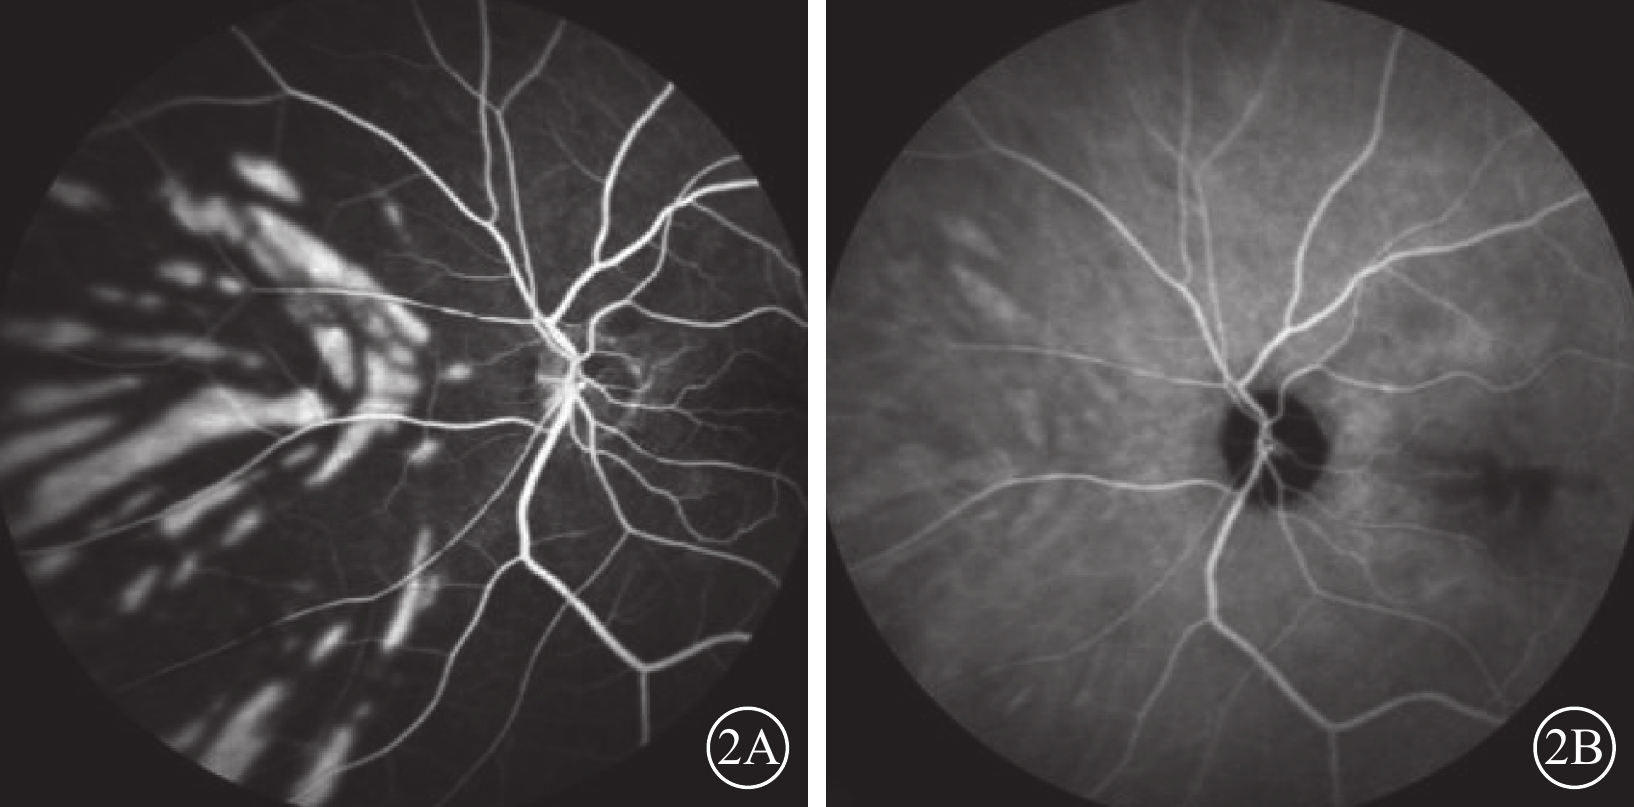

患者女,77歲。因左眼視力下降8個月加重1個月于2017年10月26日至北京大學第三醫院眼科中心就診。既往曾有晨起時一過性左眼黑矇史;否認高血壓、糖尿病等全身病史。甘油三酯輕度升高,出凝血時間正常。眼部檢查:左眼視力0.1,矯正不能提高;右眼視力0.2,矯正視力0.3。左眼眼壓(IOP)20 mmHg(1 mmHg=0.133 kPa)。晶狀體核性混濁;眼底可見黃斑前膜。右眼晶狀體混濁,其余眼前節及眼底檢查未見明顯異常。診斷:(1)左眼白內障;(2)左眼黃斑前膜。于10月28日在局部麻醉下行左眼白內障超聲乳化IOL植入、23G玻璃體切割手術(PPV)。手術參數:超聲乳化瓶高85 cm,PPV時IOP 28 mmHg。手術時間45 min,過程順利。手術后第1天,左眼視力眼前數指。角膜輕度水腫;眼底視盤邊界清楚,色澤正常,黃斑區輕度水腫。IOP 37 mmHg,給予降眼壓藥物控制。手術后第2天,患者自述晨起時左眼黑矇,檢查左眼視力上方眼前手動。眼底視盤邊界清楚,顏色淡;后極部視網膜灰白水腫,無櫻桃紅斑(圖1A),視網膜動脈內血流中斷;視盤鼻側見羽毛狀灰白水腫楔狀區域(圖1B),與視網膜血管分布不一致。IOP 18 mmHg。FFA檢查,視盤和脈絡膜充盈遲緩,視網膜中央動脈14″ 73開始充盈,可見動脈前鋒,21″17靜脈尚未完全充盈;25″92視盤鼻側開始顯現由邊界清楚羽毛狀強熒光拼成的楔形區域,隨時間延長熒光增強,但始終邊界清楚(圖2A)。次日ICGA檢查,脈絡膜充盈遲緩,至10′42″20時視盤鼻側開始出現脈絡膜強熒光區,與FFA所見形態部位一致(圖2B)。OCT檢查,視網膜內層彌漫強反射,層次不清,黃斑中心凹處呈皺褶狀隆起(圖3),鼻側病灶區脈絡膜層面異常反射不顯著。頸動脈彩色多普勒血流顯像(CDFI)檢查,雙側頸動脈硬化斑塊形成。心臟CDFI檢查,左室泵功能正常,舒張功能減低;主動脈瓣輕度關閉不全。神經內科初步診斷:頸內動脈系統短暫性腦缺血發作。頭頸部CT血管造影(CTA)檢查,雙側頸內動脈起始部血管壁混雜斑塊形成,管腔變窄。頭顱CT檢查,多發腔隙性腦梗死,軟化灶。腦白質疏松,腦萎縮。未行頭頸部數字減影血管造影。24 h橈動脈動態血壓監測結果:白天平均血壓121/60 mmHg,脈壓差60.7 mmHg;夜間平均血壓110/51 mmHg,脈壓差59.7 mmHg。最終臨床診斷:(1)左眼脈絡膜三角綜合征;(2)左眼視網膜中央動脈阻塞(CRAO);(3)左眼內低灌注。

左眼FFA、ICGA像。2A示FFA 25″92像,視盤鼻側顯現邊界清楚羽毛狀條形強熒光灶,總體拼成楔形區域,尖端指向視盤;2B示ICGA10′42″20像,視盤鼻側開始出現脈絡膜強熒光區,與FFA所見形態部位一致

左眼FFA、ICGA像。2A示FFA 25″92像,視盤鼻側顯現邊界清楚羽毛狀條形強熒光灶,總體拼成楔形區域,尖端指向視盤;2B示ICGA10′42″20像,視盤鼻側開始出現脈絡膜強熒光區,與FFA所見形態部位一致

圖2

左眼FFA、ICGA像。2A示FFA 25″92像,視盤鼻側顯現邊界清楚羽毛狀條形強熒光灶,總體拼成楔形區域,尖端指向視盤;2B示ICGA10′42″20像,視盤鼻側開始出現脈絡膜強熒光區,與FFA所見形態部位一致

圖2

左眼FFA、ICGA像。2A示FFA 25″92像,視盤鼻側顯現邊界清楚羽毛狀條形強熒光灶,總體拼成楔形區域,尖端指向視盤;2B示ICGA10′42″20像,視盤鼻側開始出現脈絡膜強熒光區,與FFA所見形態部位一致

討論 本例患者于PPV后第2天出現左眼急性黑矇,眼底表現后極部彌漫水腫,部分血管血流中斷,未見櫻桃紅斑典型改變。提示除視網膜中央血管缺血外,還存在其他病變。視盤鼻側邊界清楚羽毛狀水腫楔形區,與視網膜血管走形不一致,說明水腫來源于脈絡膜缺血。FFA和ICGA檢查提示眼內灌注不良,視盤鼻側呈邊界清楚地羽毛狀強熒光楔形區域,支持脈絡膜的缺血梗死。根據以上癥狀體征,患者左眼脈絡膜三角綜合征、CRAO、眼內低灌注診斷成立。